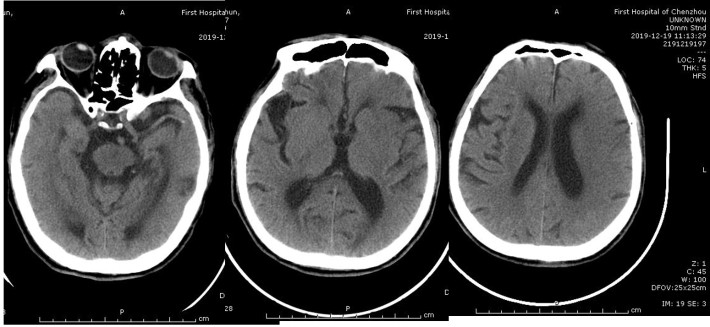

患者发病到入院时间超过4.5h时间,静脉溶栓时间窗超过,考虑大血管病变,患者急诊CT提示左侧大脑中动脉高密度征,ASPECTS评分9分,未见明显低密度灶,结合患者急诊查体,高度提示左侧颈内动脉系统大动脉闭塞。与家属沟通后,急诊行DSA,必要时予血管内治疗。

急诊头颅CT:左侧大脑中动脉高密度征,

ASPECT评分:9分。